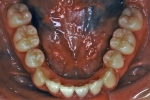

治療中